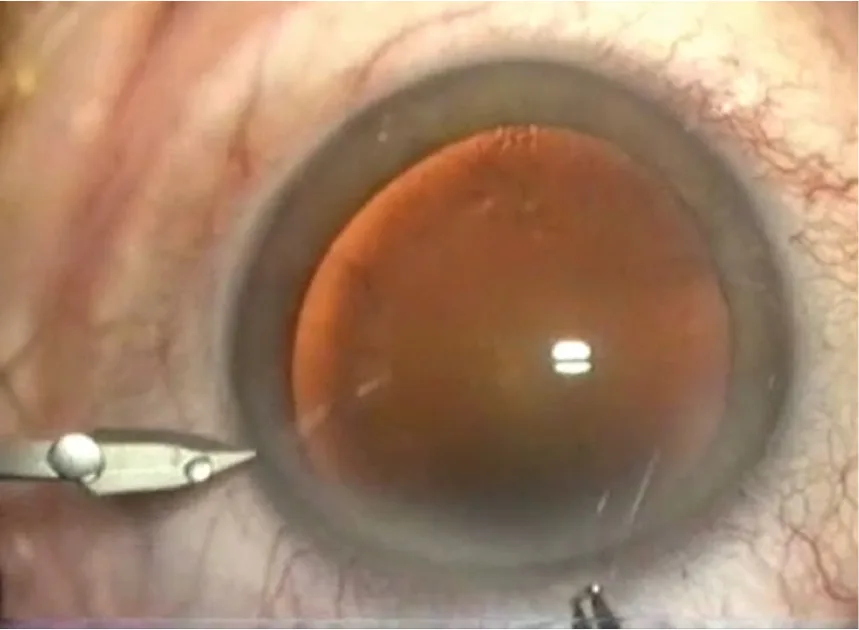

Figure 3.2. Micro-incision de 1,4 mm pour phacoémulsification biaxiale.